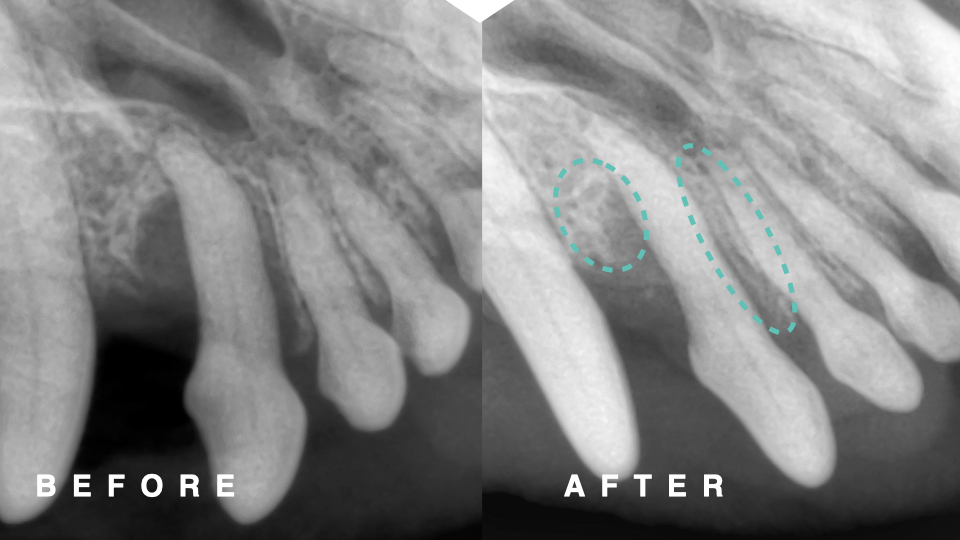

下の写真は処置時の歯槽骨と術後1.5ヶ月の歯科レントゲン写真です。

上顎切歯の吻側の歯槽骨が再生している所見が認められます。また、尾側の骨欠損部位も骨増生が認められ、

歯周ポケットの深さも6mmから3mmに改善し、診断は重度歯周病(AL81%)から軽度歯周病(AL22%)まで改善しました。